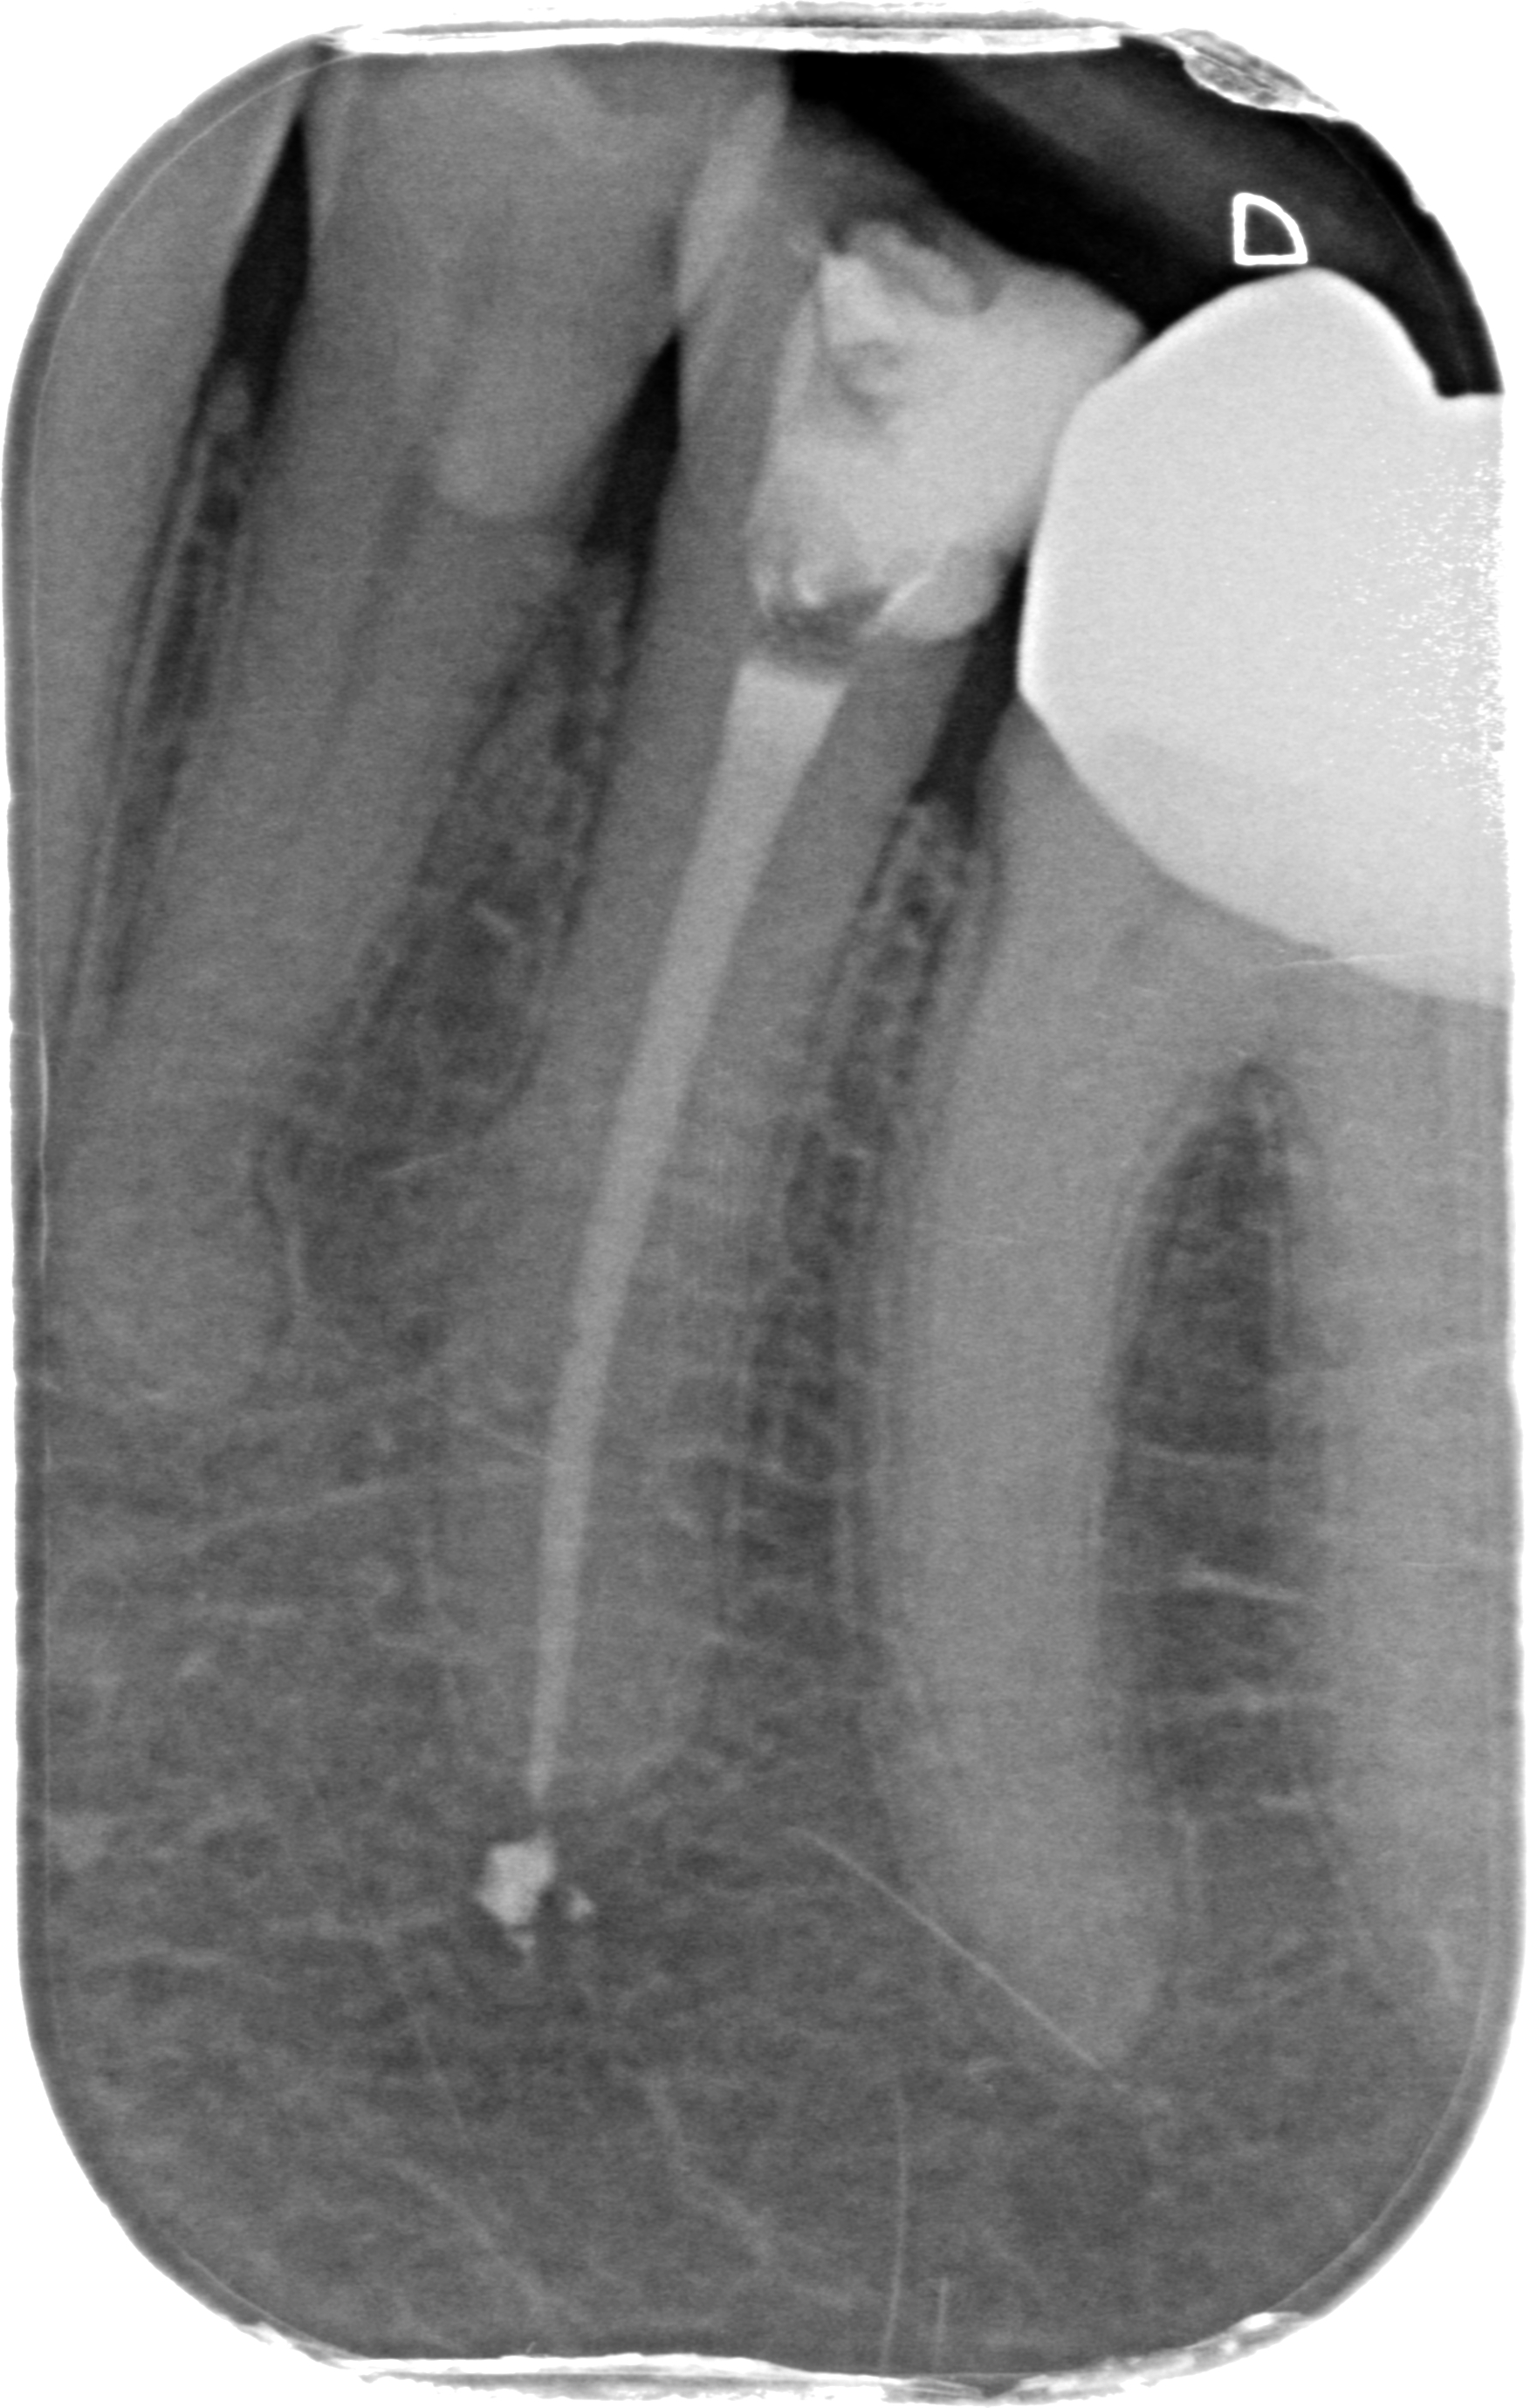

Elemento dentale 3.5 che presenta una terapia canalare non corretta.

Dopo

Elemento dentale 3.5 una volta ritrattato. Si evidenzia la chiusura del canale fino alla fine dell'apice radicolare.